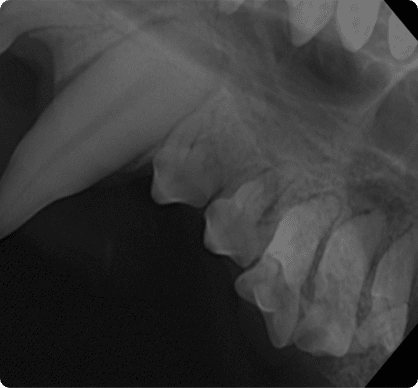

치태 및 치석에 존재하는 구강 세균이

치아 주변 조직인 잇몸과 잇몸뼈를 파괴하는 가장 흔한 질환